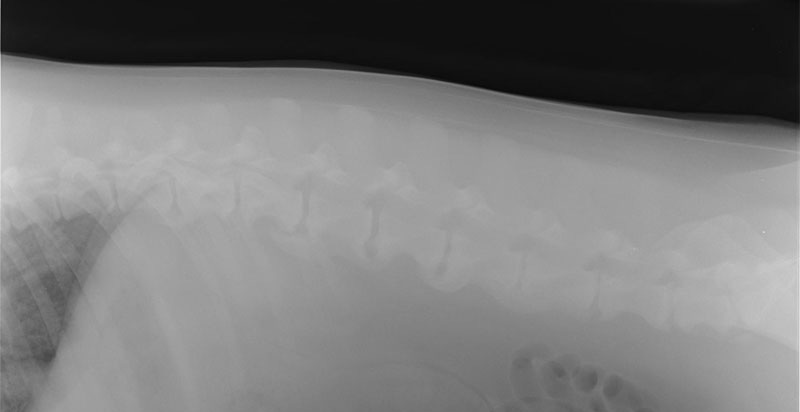

レントゲン検査

通常見ることのできない内臓の大きさや形、配置の変化を調べます。

心臓病、肺や気管・気管支の状態、腹腔内諸臓器の大きさや形の変化、腫瘍や結石の有無などがわかります。

変形性関節症・変形性脊椎症

背骨の骨同士が癒合しています。(8歳、G・R)